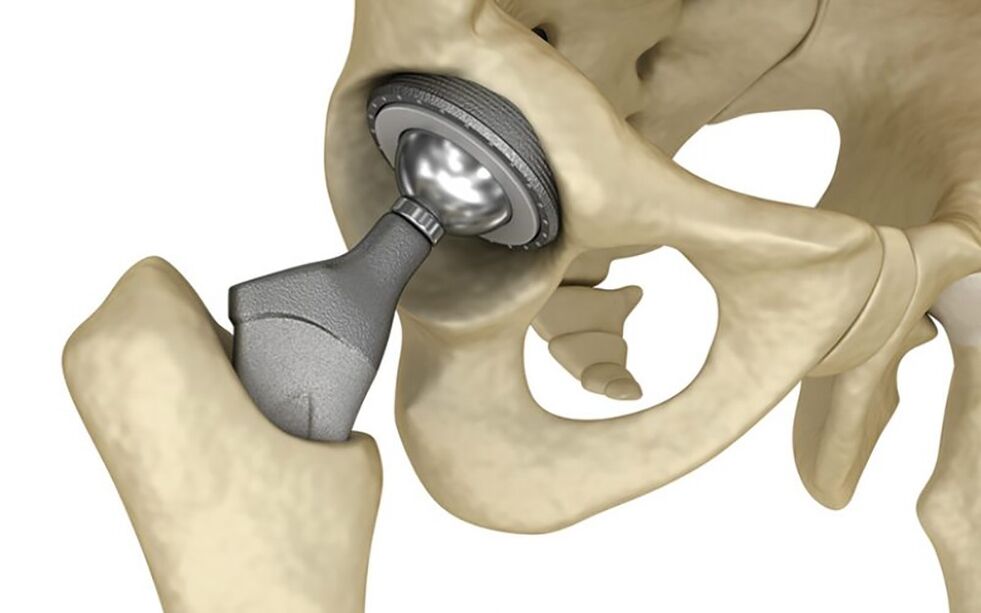

Hüftersatz

Die einzige Möglichkeit zur vollständigen Wiederherstellung des Hüftgelenks im dritten Stadium der Coxarthrose ist eine Operation – Endoprothetik (Atroplastik) des Hüftgelenks.

Die Endoprothese besteht aus zwei Komponenten: einem Kopf und einer Pfanne.

Diese Operation ist nicht einfach:

- Nach der Operation ist eine lange Rehabilitationszeit erforderlich.

- Die Heilung des Gelenks ist schmerzhaft (der Schmerz kann ein Jahr lang anhalten).

- Sie müssen einige Zeit mit Hilfe einer Gehhilfe oder einem Stock als Stütze gehen.